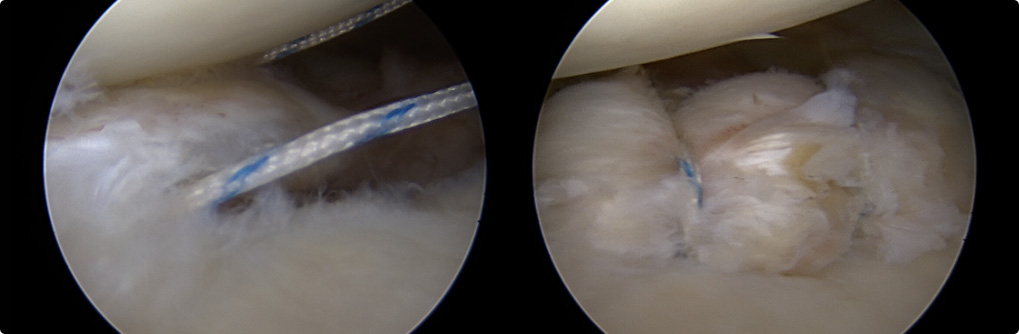

관절와순 봉합술

관절 내시경을 통해 파열된 관절와순을 정상적인 모양으로 봉합하여 제 기능으로 회복시켜 줍니다.